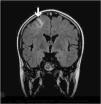

Una niña de 12 años de edad, sin antecedentes patológicos de interés es diagnosticada de disgerminoma supraselar por un cuadro de panhipopituitarismo. Fue sometida a una resección transesfenoidal parcial y posteriormente comenzó con un tratamiento quimioterápico, de cisplatino, etopóxido y bleomicina. Una semana después de recibir el primer ciclo, inicia un cuadro progresivo de cefalea holocraneal intensa que interfiere con el sueño, junto con náuseas, visión borrosa y dificultad para mover las extremidades izquierdas. En la exploración neurológica se observaron una hemiparesia izquierda leve (síndrome faciobraquiocrural) y un papiledema bilateral en la exploración del fondo de ojo. Se practicó una tomografía computarizada (TC) craneal que fue normal y se procedió al ingreso de la paciente. En las horas siguientes sufrió una progresión del cuadro con aparición de tetraparesia de predominio izquierdo y crisis parciales motoras con generalización secundaria, por lo que se decidió su ingreso en la unidad de cuidados intensivos pediátricos. Se practicó una resonancia magnética (RM) craneal con secuencias de angiorresonancia (2DTOF) que demostró la existencia de áreas de restricción de la difusión en región motora cortical bilateral, imagen compatible con un infarto venoso cortical derecho y una trombosis de los senos longitudinal, sigmoide y transverso derechos, así como del seno transverso izquierdo (figs. 1 y 2). El resto de estudios complementarios fueron normales. Las crisis fueron controladas con anticonvulsionantes y la paciente fue tratada con medicación anticoagulante durante 3 meses. En el momento del alta no se apreciaron secuelas neurológicas en ninguna localización y durante el año de seguimiento posterior la paciente ha permanecido asintomática. Las RM de control realizadas a los 3 y a los 6 meses fueron normales.